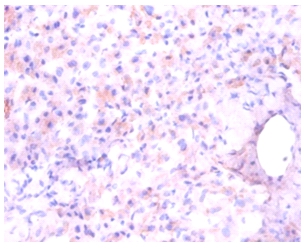

Immunohistochemical analysis of paraffin-emdedded human liver using #42384 at dilution of 1:100.